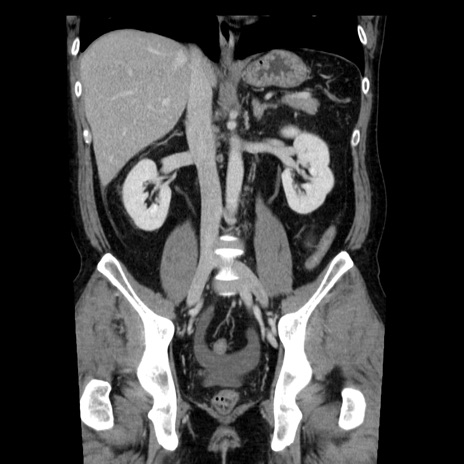

症例29(冠状断像)

【症例】40歳代男性

【現病歴】2日前から胃痛あり。徐々に周期的な激痛に変化した。本日になっても激痛があるため受診。

【身体所見】意識清明、BT 38-39℃台あり、腹部:膨満、やや硬、右下腹部に圧痛あり。

【データ】WBC 8500、CRP 23.26